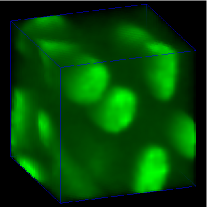

Our proposed method was compared to other 3D segmentation methods including 3D active surface [7], 3D active surface with inhomogeneity correction [8], 3D Squassh [9, 10], 3D encoder-decoder architecture [20], 3D encoder-decoder architecture with CycleGAN. Three original 3D subvolumes of Data-I were selected to evaluate the performance of our proposed method. We denote the original volume as subvolume (), subvolume (), and subvolume (), respectively. Corresponding groundtruth of each subvolume was hand segmented. Voxx [29] was used to visualize the segmentation results in 3D and compared to the manually annotated volumes. In Figure 5, 3D visualizations of the hand segmented subvolume and the corresponding segmentation results for various methods were presented. As seen from the 3D visualization in Figure 5, our proposed method shows the best performance among presented methods visually compared to hand segmented groundtruth volume. In general, our proposed method captures only nuclei structure whereas other presented methods falsely detect non-nuclei structures as nuclei. Note that segmentation results in Figure 5 yields smaller segmentation mask and suffered from location shift. Our proposed method shown in Figure 5 outperforms Figure 5 since our proposed method uses spatially constrained CycleGAN and takes consideration of the Dice loss and the binary cross-entropy loss.